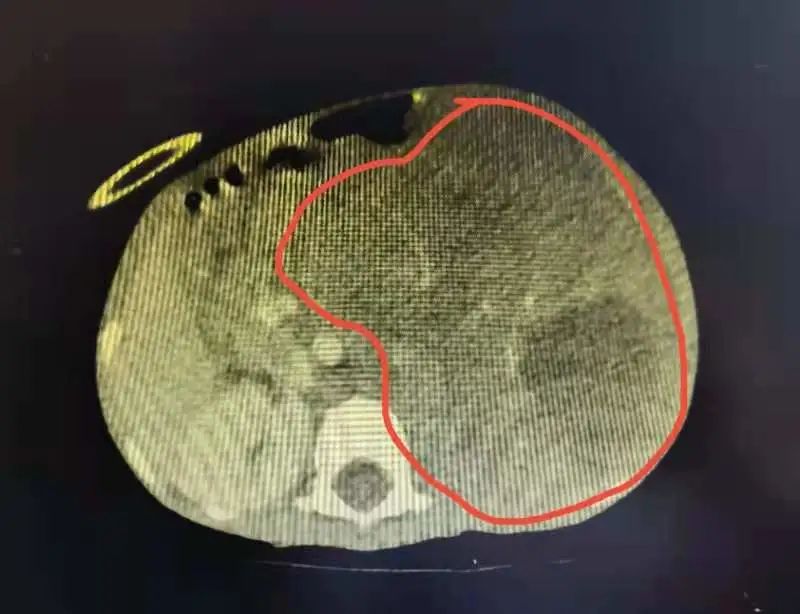

3岁女孩只有10公斤肿瘤充满腹腔

图片尺寸800x614